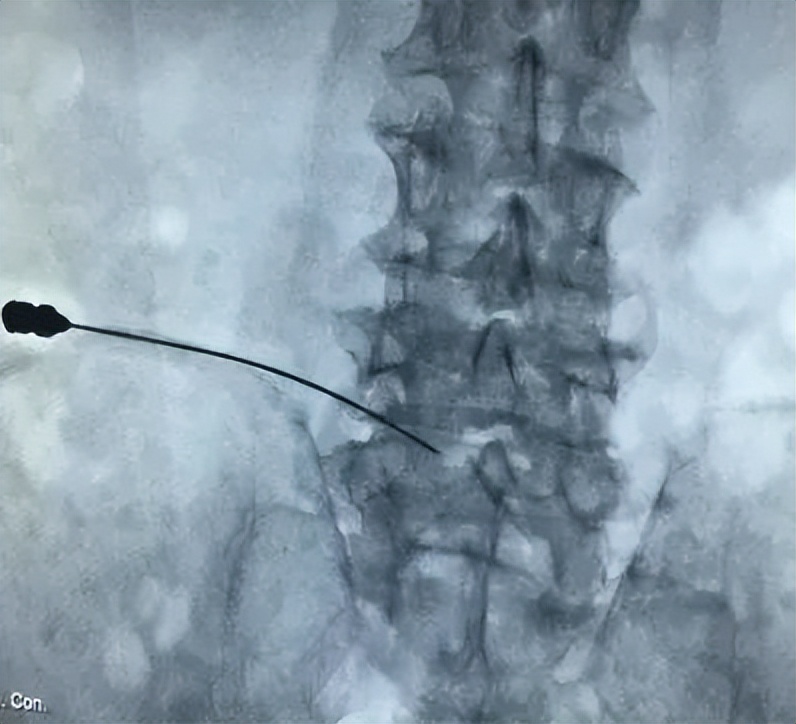

射频热凝靶点治疗术是治疗椎间盘突出症最先进的方法。射频热凝靶点治疗是C型X光机下准确定位,数字减影下时时监测,导航系统的精确引导下直接把突出部位的髓核变性、凝固,收缩减小体积,解除压迫。该治疗方式不伤及正常的髓核组织,同时修补了纤维环的破裂、灭活了盘内新生病变超敏的神经末梢,直接阻断了髓核液中糖 蛋白和β蛋白的释放,温热效应对损伤的纤维环、水肿的神经根、椎管内的炎性反应起到良好的治疗作用,症状立即消失或减轻。

射频靶点热凝术是通过一根很细的特有穿刺针穿刺到突出病变部位,局部通过高频率射频电流,使细胞在不同温度下产生热凝调节。使突出的椎间盘收缩、体积减小,立即解除对神经根及窦椎神经的压迫,修复破裂的纤维环、灭活性因子及致痛因子,促进局部血液循环以达到解除腰腿痛的目的,手术顺利完成。这是目前国际上最微创、最安全、病人痛苦最小、见效最快、风险最低的一种治疗方案。